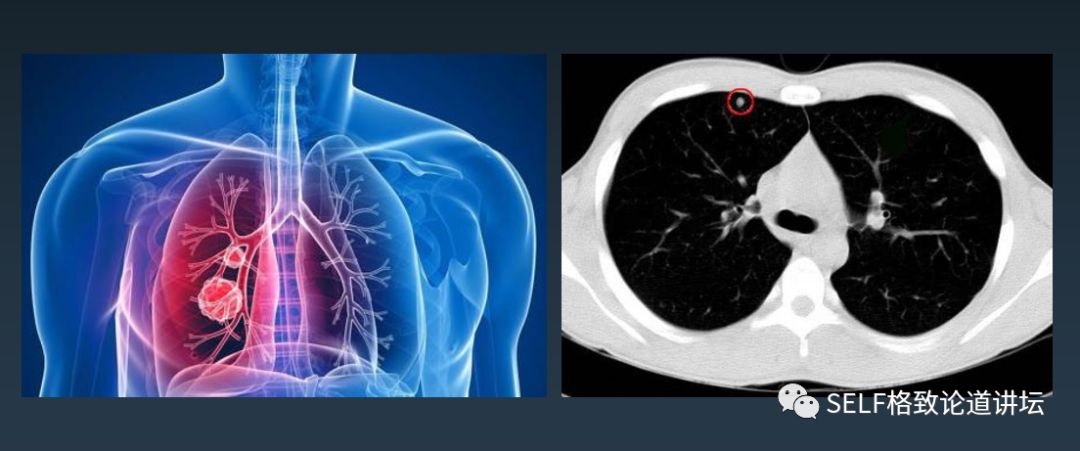

第二个故事,几年前,我去参观一台机器人做的手术。当时这个患者有一个肺部结节,手术前,医生通过一些染料在患者身体的结节周围打了一圈标记。

但是在手术过程中这些标记找不到了,最后通过医生丰富的经验去判断,还是艰难地找到了标记。

这反映了一个问题,即便你的手很灵巧,但如果你的眼睛看不到组织表面以下的这些病变,还是做不好手术的,手术依然困难。

左边是教科书上能够看到的,人的组织器官分得非常鲜明,血液都是有颜色的。

右边是医生看到的画面,所有的组织器官全都是摞在一起的,无法区分血管和病变。

随着技术的进步,也为手术机器人带来了一些突破。像图中就是用一种染色的办法,通过荧光成像,把它的图采集回来,这样手术机器人就可以看到病变在哪里。